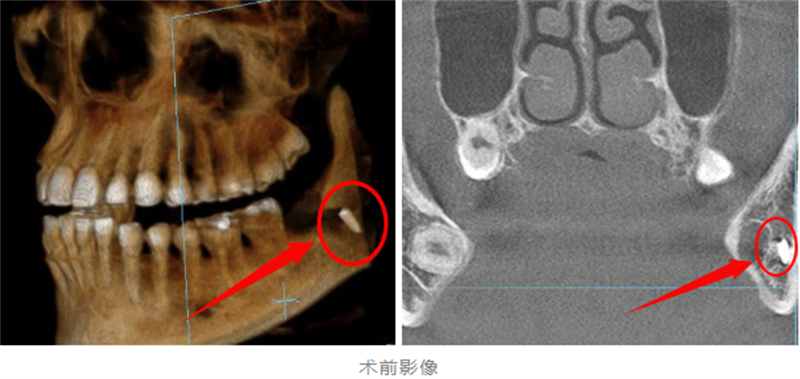

年僅28歲的王女士(化名)日前在某私人診所拔除下頜阻生智齒后,出現(xiàn)持續(xù)性口腔疼痛及異物感。察覺異常后,她緊急前往柳州市人民醫(yī)院口腔科就診。經(jīng)CBCT(錐形束CT)影像檢查顯示,疑似拔牙器械尖端殘留于下頜骨內(nèi),且大部分嵌入下牙槽神經(jīng)管區(qū)域,由于此處位置深在,鄰近重要血管、神經(jīng),手術(shù)取出難度極大。

據(jù)了解,此次患者殘留的器械尖端緊鄰下牙槽神經(jīng),若不及時取出,可能導(dǎo)致永久性神經(jīng)損傷。而由于初次拔牙術(shù)后軟組織水腫、開口受限,二次手術(shù)操作空間極為狹小,對醫(yī)生的技術(shù)精度提出了極高要求。